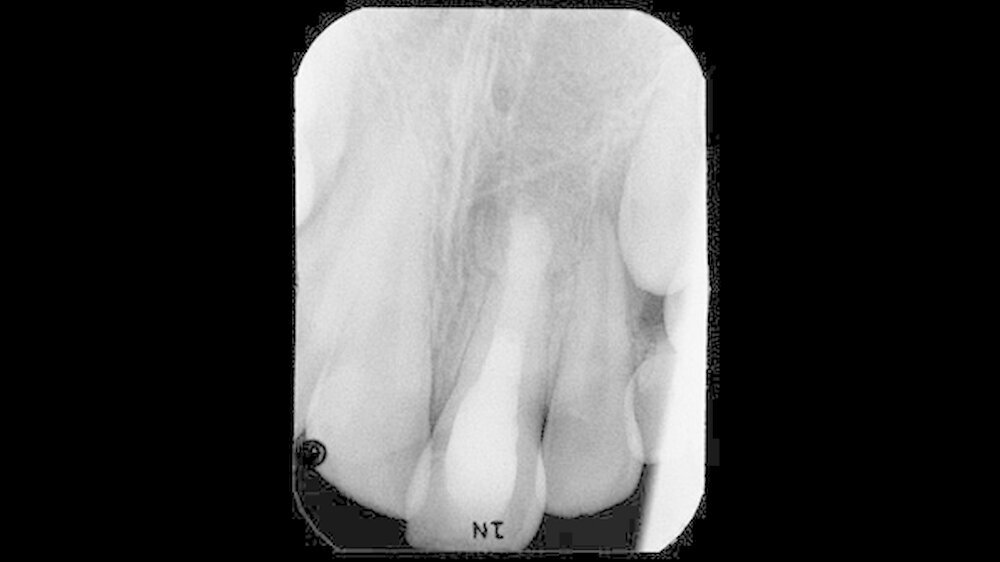

Das nach 22 Monaten angefertigte Röntgenbild (Abbildung 4) zeigt eine nahezu vollständige Regeneration der bei Behandlungsübernahme bestehenden apikalen Osteolyse. Trabekelstrukturen im vorherigen Lumen lassen eine Ausheilung des Knochendefekts vermuten. Ein Längen- beziehungsweise Dickenwachstum der Wurzel lässt sich nicht erkennen. Ob durch weitere Einlagen von Kalziumhydroxid ein vollständiger apikaler Verschluss erreicht werden kann, erschien nach der bislang schon langen Behandlungszeit fraglich.

Aus diesem Grund bot sich der apikale Verschluss mit dem bioaktiven, alkalischen Zement Biodentine an; einem Kalziumsilikatzement von Septodont. Unter dem Operationsmikroskop konnte das Biodentine unter Sicht eingebracht und blasenfrei adaptiert werden.

Das apikale Drittel des Wurzelkanals wurde mit dem Zement verschlossen. Nach der Aushärtung von zirka 15 Minuten wurde das verbleibende Wurzelkanallumen mit einem dentinadhäsiv verankerten Komposit gefüllt und die klinische Krone rekonstruiert. Das bis über das Knochenniveau nach apikal reichende Komposit soll hier adhäsiv die durch geringe Hartsubstanz geschwächte Wurzel zur Frakturvermeidung stabilisieren. Das abschließend angefertigte Röntgenbild (Abbildung 5) zeigte eine Randdichte und blasenfreie Obturation des Wurzelkanallumens.

Die Aufnahme ist 25 Monate nach Behandlungsübernahme angefertigt worden. Im Vergleich zur Voraufnahme ließ sich eine weitere Ausheilungstendenz und Zunahme der Radioopazität im Bereich der vorherigen apikalen Osteolyse erkennen.